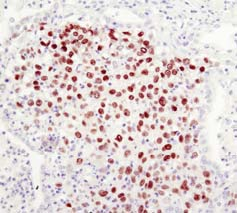

左:基于生物素的检测; 右:基于聚合物的检测

相对于基于生物素的检测而言,基于聚合物的检测的敏感性更高。

利用Sox2 (D6D9) XP® Rabbit mAb #3579 对石蜡包埋的人类肺部肿瘤进行IHC分析,采用基于生物素的检测(左)或基于聚合物的检测(SignalStain® Boost IHC Detection Reagent #8114;(右)。如图所示,基于聚合物的检测敏感度更高,染色强度更好。